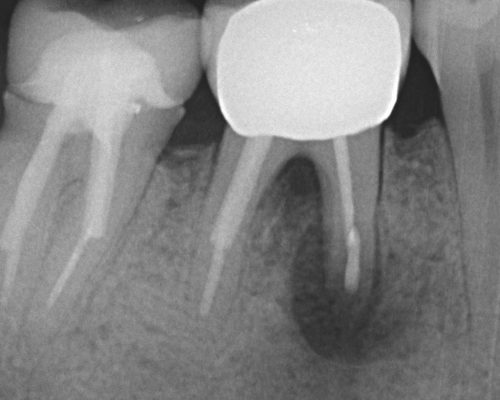

kindtand lige efter roidspidsoperation

Efter rodspidsoperation

Rodspidsoperation af kindtand